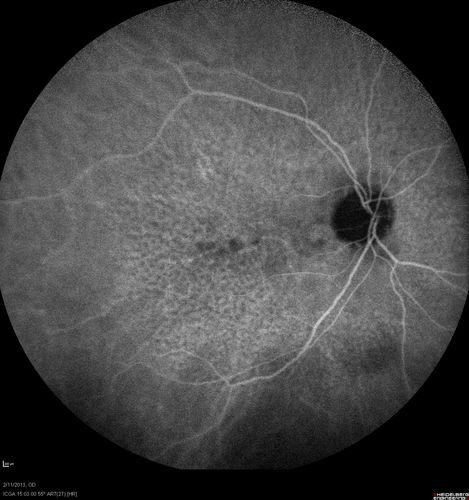

Asymptomatic Juxtapapillary Choroidal Neovascular Membrane - Reticular Macular Disease (Wet AMD)

Asymptomatic Juxtapapillary Bilateral Wet AMD - Reticular Macular Disease - Heidelberg Color Photos